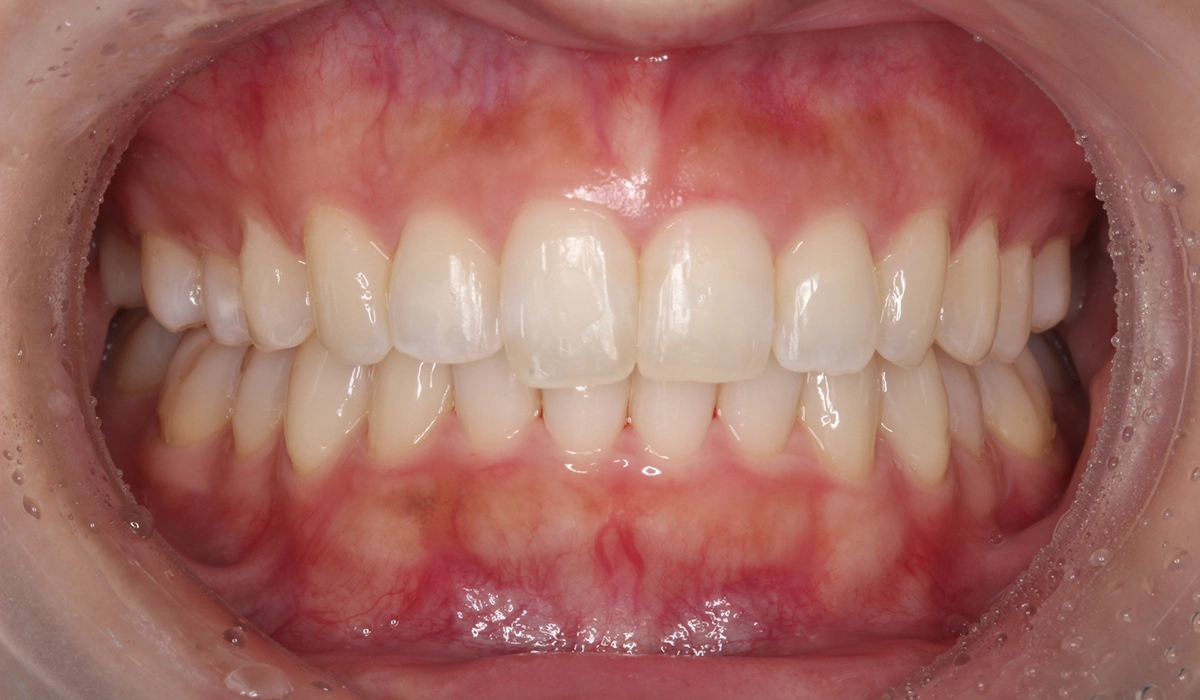

術後:正面

非抜歯と可能な限りIPRなしにこだわったため、大臼歯の遠心移動を主体としてスペースを確保したため治療期間がやや長くなるも18カ月で完了致しました。

| 治療期間 | 18カ月 |